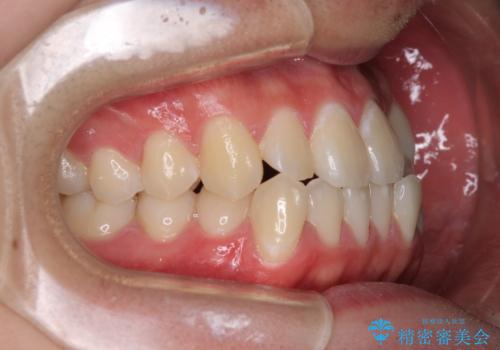

受け口傾向の骨格であり、前歯はクロスバイトまたは切端咬合となっており、叢生は警備であったため、下顎を中心に歯列全体の後方移動を行い、IPR(歯と歯の間を削る)によってデコボコが解消するように設計し、インビザラインにより治療を行うこととしました。

受け口傾向のインビザライン矯正は比較的治療を行いやすいため、きれいに仕上げることができました。舌の突出癖が顕著であったため、改善のためのトレーニングをしっかりと行っていただきました。